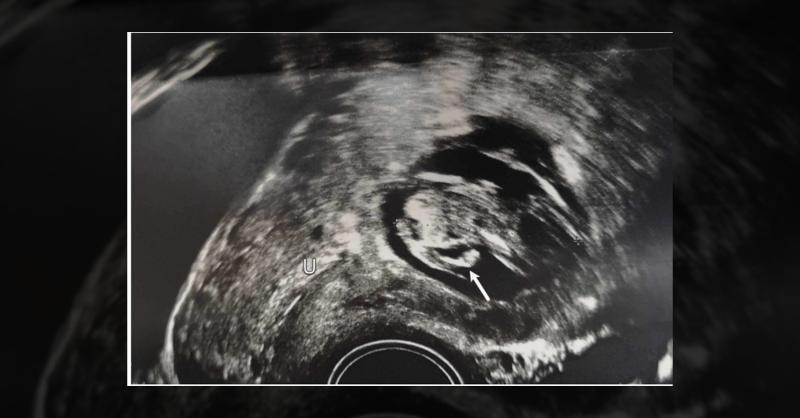

Management of Cesarean Scar Ectopic Pregnancy in a 44-Year-Old Woman

A 44-year-old woman presented after six weeks of amenorrhea, confirming pregnancy through a positive urine β-hCG test. She had a history of four live births via low-transverse cesarean section without previous miscarriages or ectopic pregnancies, with the first two cesarean sections due to failure to progress. Her last pregnancy was four years ago.